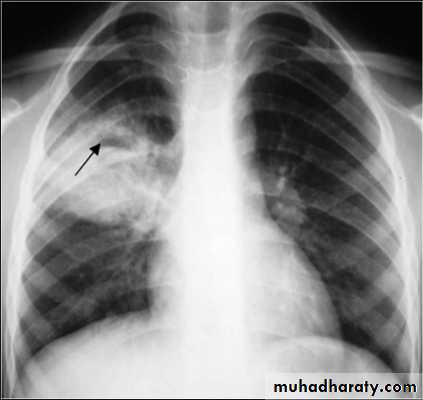

Kerley A lines (Arrows), Kerley B lines (arrowheads)

chest practice